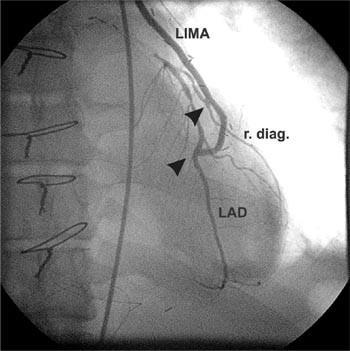

Hos 18 pasienter ble a. radialis eller høyre a. mammaria koblet ende-til-side til venstre a. mammaria som T-graft, slik at hele hjertet kan revakulariseres med et graftsystem (fig 1). I 23 tilfeller ble en arterie brukt til flere koblinger med koronararteriene (sekvensanastomose) (fig 2). Hos seks pasienter ble det i tillegg til arterielle graft supplert med venegraft til mindre koronarkar.

T-graft revaskularisering med a. radialis eller a. mammaria . De fleste pasienter som aksepteres til koronarkirurgi har trekarssykdom med behov for tre eller flere bypass. Sammenliknet med venemateriale er lengden av hvert enkelt arteriegraft begrenset. Selv om flere arterier er tilgjengelige, er høstingen tidkrevende. En måte å kompensere for manglende lengde er å bruke T-graft eller Y-graft. A. radialis eller høyre a. mammaria kobles da ende-til-side til venstre a. mammaria (fig 1). Metoden ble først beskrevet i 1994 av Tector og medarbeidere (27). Det er vist at man ved å bruke slike graft kan oppnå komplett arteriell revaskularisering. Bruk av T-graft reduserer instrumentering av aorta ascendens fordi proksimale anastomose sys direkte til a. mammaria. Metoden bidrar derfor muligens til å redusere forekomsten av nevrologiske komplikasjoner hos pasienter med aterosklerose i aorta ascendens. Det foreligger foreløpig mangelfull dokumentasjon på langtidsresultater av denne metoden (27, 28).